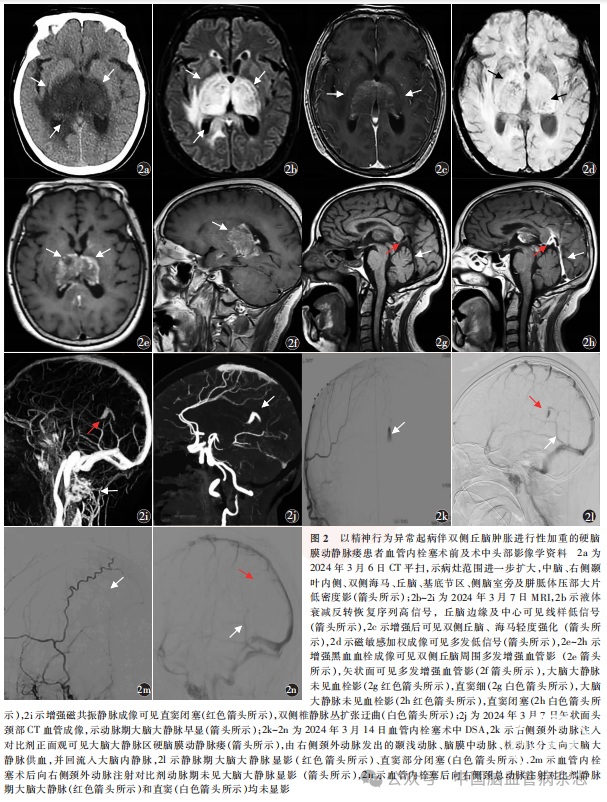

入院当日(2024年3月6日)行腰椎穿刺术,脑脊液初压110mmH2O;脑脊液检查示,外观无色透明,蛋白定量67.4mg/L(参考范围15.0 ~ 45.0mg/ L),IgA0.93mg/L (参考范围0 ~ 0.20mg/L)、IgM0.21mg/L(参考范围0 ~ 0.20mg/L),IgG7.54mg/L(参考范围0.48~5.86mg/L)。视神经鞘多普勒、颈静脉彩色多普勒均未见异常;下肢深静脉彩色多普勒示右侧小腿肌间静脉血栓(亚急性期,部分型)。头部CT平扫示病灶范围进一步扩大,中脑、右侧颞叶内侧、双侧海马、丘脑、基底节区、侧脑室旁及胼胝体压部大片低密度影(图2a)。2024年3月7日,CTP示病灶处脑血流量、脑血容量减低,相应平均通过时间、达峰时间血流灌注延迟;头部MR示病灶区T1加权成像稍高或低信号,T2加权成像高信号,液体衰减反转恢复序列高信号,丘脑边缘及中心可见线样低信号(图2b),扩散加权成像示等或低信号,ADC值减低,增强后双侧丘脑、海马轻度强化(图2c);磁敏感加权成像(susceptibility weighted imaging, SWI)多发低信号(图2d);磁共振黑血血栓成像(magnetic resonance black-blood thrombus imaging, MRBTI)示双侧丘脑周围多发增强的血管影,直窦闭塞,未见血栓征象(图2e~2h);增强MRV示直窦未显影,双侧椎静脉丛扩张迂曲(图2i);头颈部CTA示动脉期大脑大静脉早显(图2j)。因此,排除了直窦血栓的诊断,初步考虑为DAVF,拟于2024年3月14日行血管内栓塞术。术中DSA示右侧颈外动脉注入对比剂后可见大脑大静脉区DAVF,由右侧颈外动脉发出的颞浅动脉、脑膜中动脉、枕动脉分支向大脑大静脉供血,并回流入大脑内静脉(图2k),同时可见静脉期大脑大静脉显影、直窦部分闭塞(图2l),进一步明确大脑大静脉区DAVF的诊断,立即行血管内栓塞治疗。超选入右侧脑膜中动脉岩支远端后注胶,胶未弥散至静脉,栓塞后造影示动脉期大脑大静脉未再显影(图2m),静脉期大脑大静脉和直窦均未显影(图2n)。